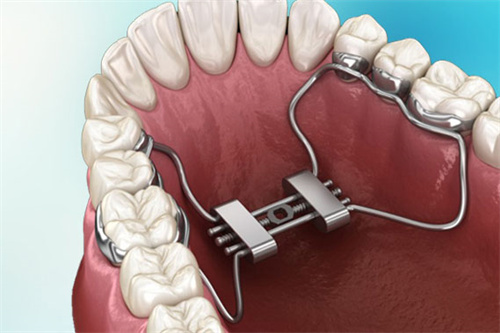

MSE(Maxillary Skeletal Expander)上颌骨骨性扩弓器,作为一种新型的正畸治疗工具,近年来在口腔医学领域受到了广泛关注。

它由美国UCLA大学的Dr. Moon医师发明,主要用于解决上颌横向发育不足(牙弓狭窄)的问题,尤其适用于青春发育期后及腭中缝已经闭合的成人患者。

MSE扩弓器通过微种植钉辅助,实现了对上颌骨的快速扩展,为患者带来了显著的治疗结果。

MSE扩弓器能够显著扩大上颌基骨宽度,改善腭中缝的宽度,同时增加上颌牙弓宽度。研究表明,使用MSE扩弓器后,上颌基骨宽度、牙弓宽度及鼻腔容积等指标均有明显提升。

与传统的Hyrax扩弓器相比,MSE扩弓器对牙槽骨的影响较小,不会导致明显的牙根长度变化或牙槽骨吸收。这使得MSE扩弓器在治疗过程中更加安心、可靠。

MSE扩弓器的设计较为简单,操作方便。它的加力过程需要遵循一定的时间表和力度要求,但总体上不需要复杂的外科手术,减少了患者的痛苦和改善时间。